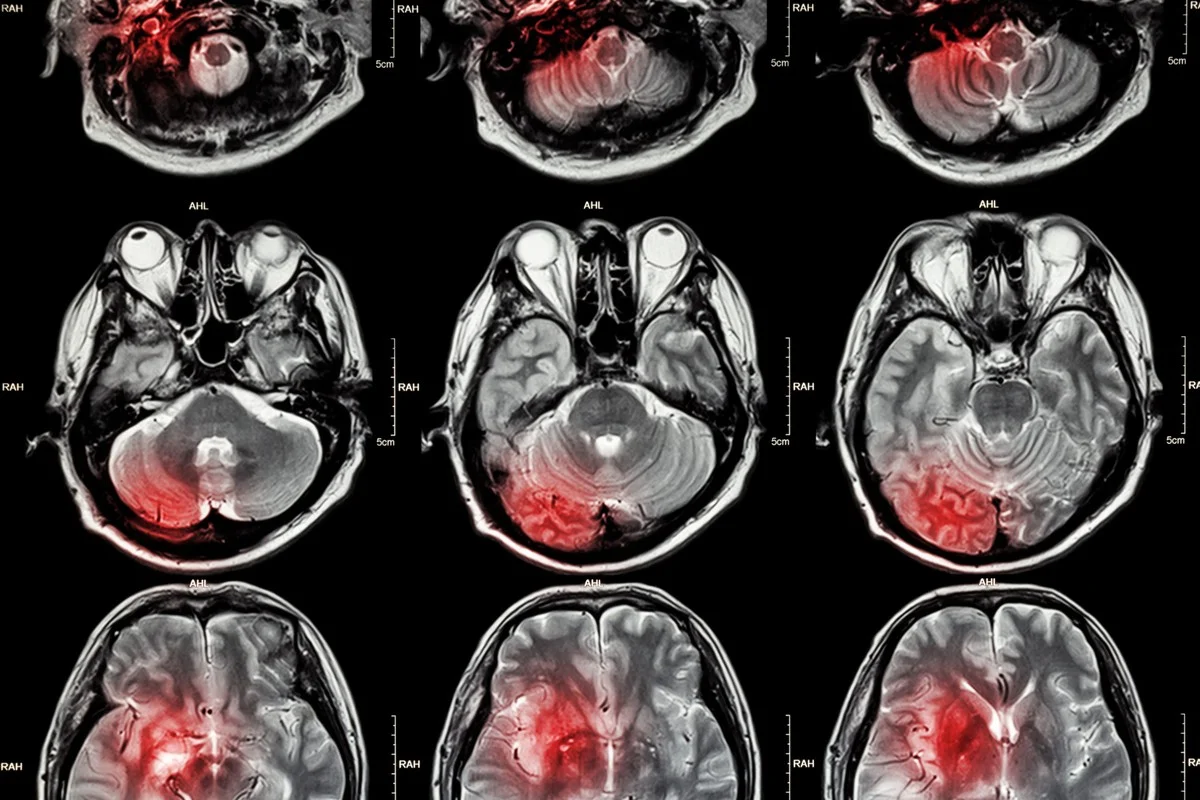

Mrtvice. Slovo, které nahání hrůzu. Když se ucpe cévka v mozku, hrozí trvalé poškození. Lékaři dnes dokážou cévy zprůchodnit, ale to samotné může spustit další katastrofu – zánět, který ničí další mozkové buňky. A právě tady přichází na scénu **zázrak moderní medicíny**, který dokáže toto poškození minimalizovat.

V klinických studiích na myších ukázala jediná dávka těchto „tančících molekul“ dramatické snížení tkáňového poškození. Vědci sledovali obrovské zmenšení infarktové oblasti oproti kontrolní skupině.

Tančící molekuly míří do mozku po mrtvici: Nová naděje pro regeneraci - image 1